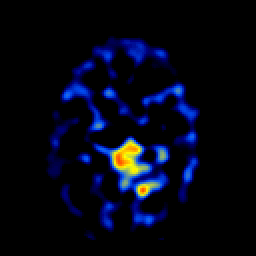

SPECT TL Study #6 -- Slice #42

[Home][Help][Clinical][Tour 1][Tour 2][Tour 3] Slice 42